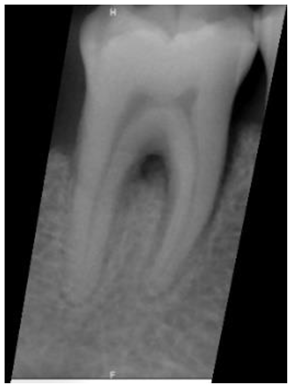

| Original Images | Gaussian High-Pass Filter | Gaussian High-Pass Filter + Mask | |

|---|---|---|---|

| Validation Accuracy | 84.16% | 87.21% | 94.97% |

| Validation Loss | 0.7634 | 0.4578 | 0.1822 |

| Model | GoogLeNet | GoogLeNet | GoogLeNet |

| Image | ![]() | ![]() | ![]() |